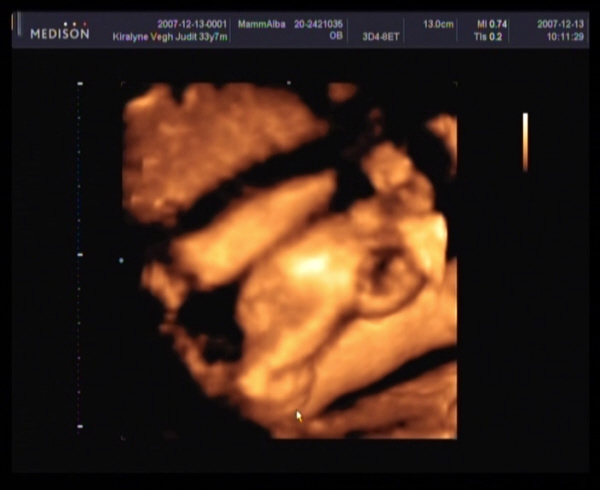

2007.12.13 12:28